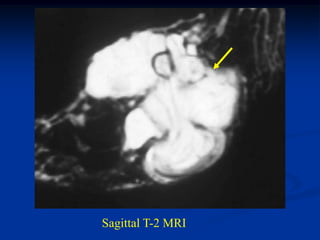

Case #302

7 month male

lymphangioma

elbow

Coronal T-1 MRI

Axial T-2 MRI

Case #302 7 monthmale lymphangioma elbow